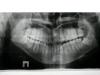

Сергей Поддубнов Опубликовано 10 сентября, 2010 Автор Поделиться Опубликовано 10 сентября, 2010 Всем, здравствуйте! Позавчера ходил в поликлинику сделал снимок. Разговаривал с врачами по поводу лечения прикуса хирургическим путем, так у нас в городе никто этим не занимается и ничего конкретного мне сказать не смогли, говорят можем вылечить брикетами, но у меня все сложнее... Вот снимок. Помогите пожалуйста! Ссылка на комментарий